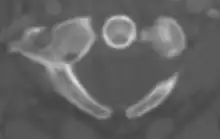

The atlas's chief peculiarity is that it has no body.[3] It is ring-like and consists of an anterior and a posterior arch and two lateral masses.

Atlas from above